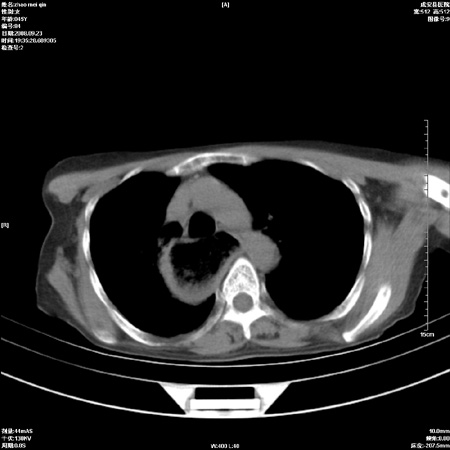

标题: CT15861:女 60 外伤后1小时 胸疼 [打印本页]

标题: CT15861:女 60 外伤后1小时 胸疼

外伤后1小时 胸疼 是外伤后引起的吗?

非外伤性改变,典型的贲门失迟缓症

食道扩张明显下端逐渐变窄,大量食物存留,象贲门失迟缓症。